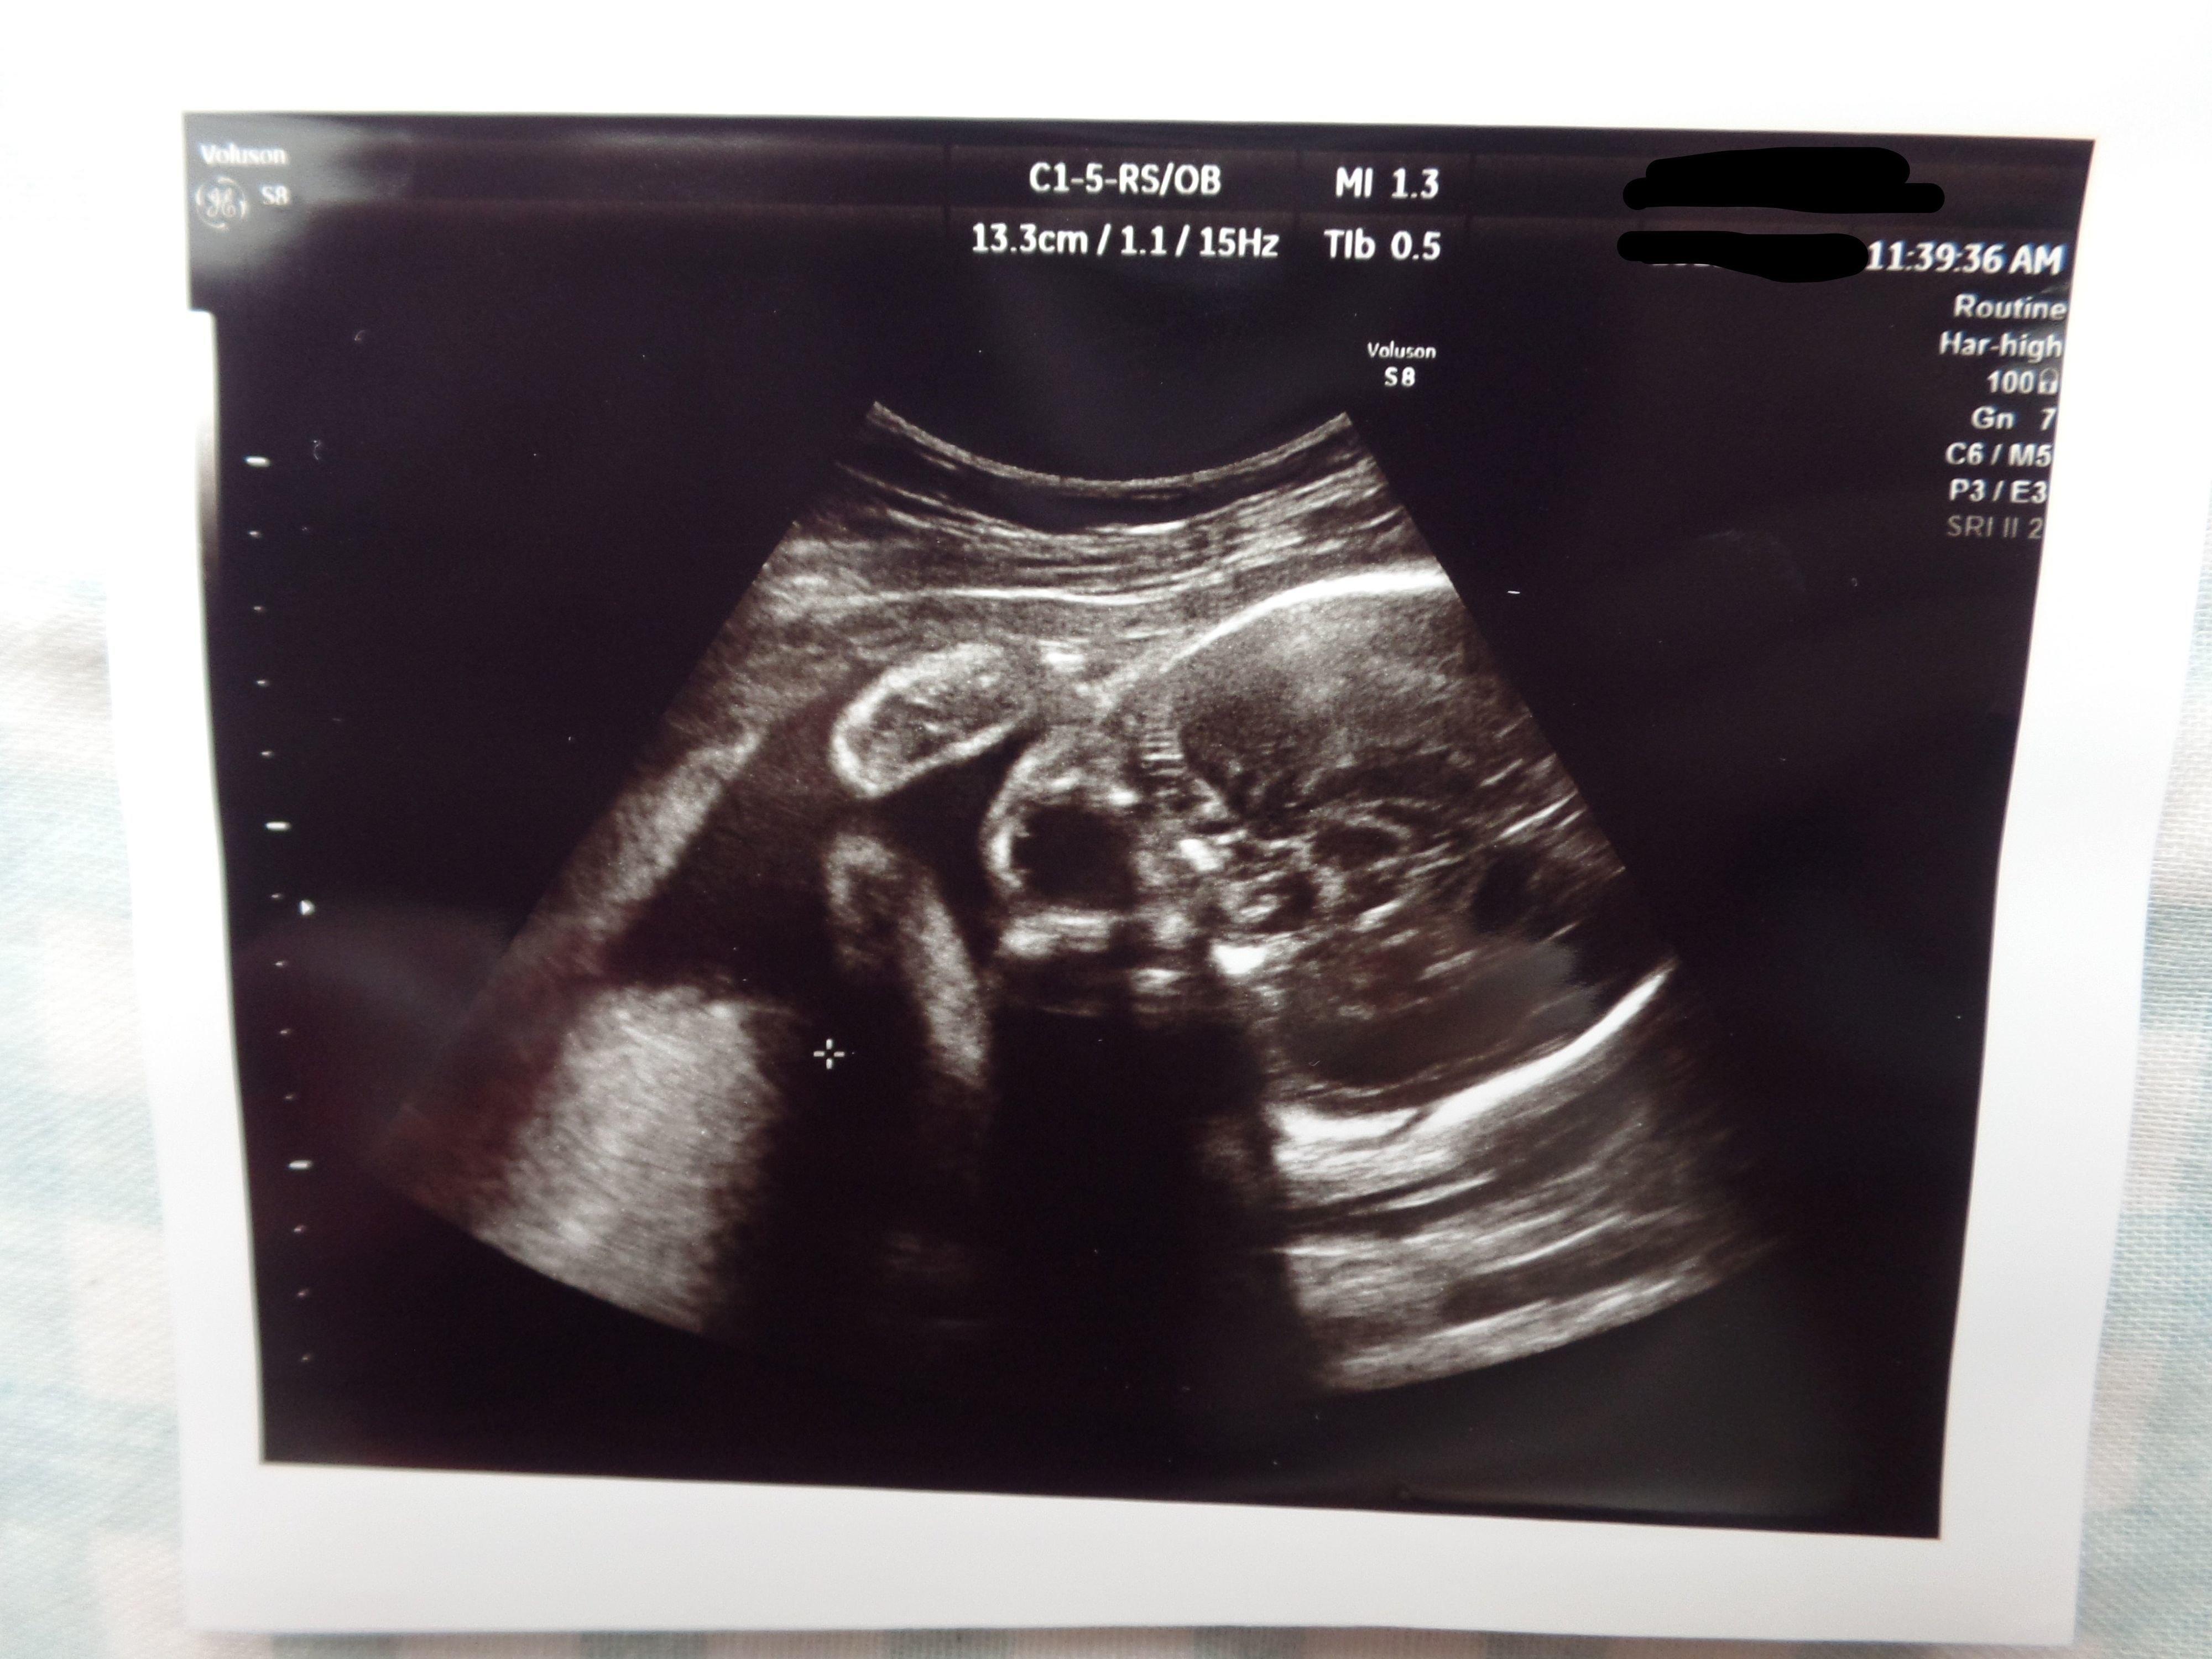

3. 多嚢胞性卵巣症候群(PCOS)から不妊治療を経て高齢出産! エコー写真で喜びを振り返る